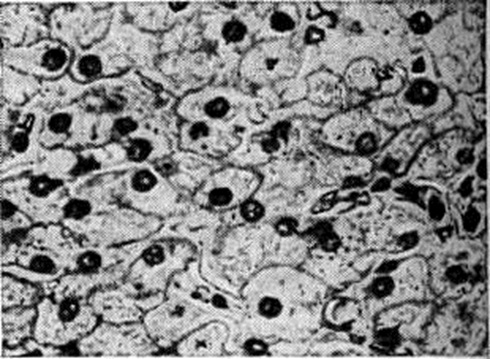

Рис. 1.

Микропрепарат печени: гликогенная инфильтрация гистиоцитов, отложение гликогена в ядрах (светлые точки). Окраска кармином Беста; × 495.

С возрастом прогрессируют гепато и нефромегалия за счёт гликогенной инфильтрации (рисунок 1), отставание в росте, диспропорция тела (большая голова, короткие шея и ноги), кукольное лицо, гипотония мышц; нарастает гипогликемический синдром натощак (больные вынуждены почти постоянно принимать пищу). Часто присоединяющиеся вторичные инфекции резко усиливают кетоацидоз (смотри полный свод знаний Ацидоз) и гипогликемию (смотри полный свод знаний) и нередко являются причиной смерти. Реже наблюдаются геморрагический синдром, кожный ксантоматоз. Нервнопсихическое развитие удовлетворительное; половое созревание значительно задерживается. Состояние больных несколько улучшается в пубертатном периоде.